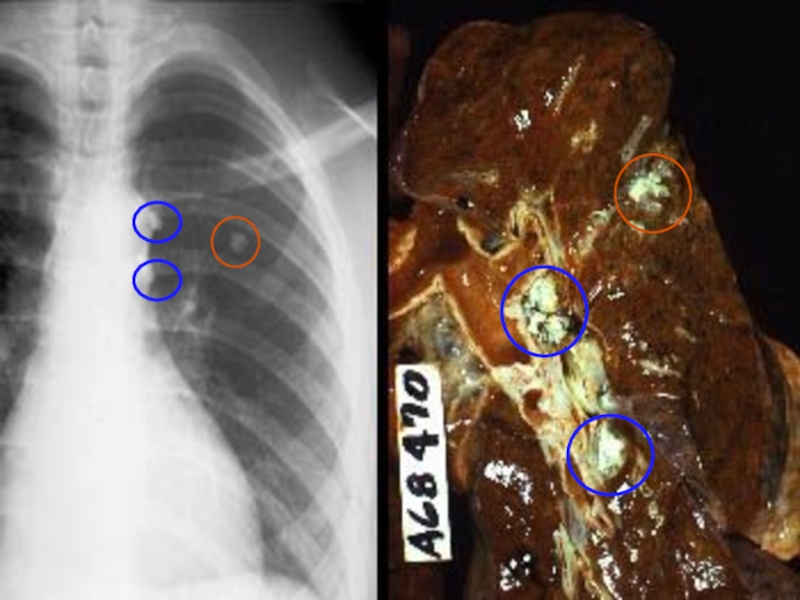

Слайд 995. Туберкулема

Округлый, ограниченный очаг > 1- 1,5 см, окруженный капсулой

R-ки

напоминает периферический рак легкого

5. Туберкулема Округлый, ограниченный очаг > 1- 1,5 см, окруженный капсулойR-ки напоминает периферический рак легкого